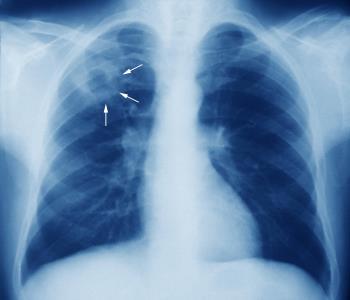

La tubercolosi è una malattia causata da determinati tipi di microbatteri che può essere trasmessa per via aerea quando le persone ammalate tossiscono. Secondo l’Ufficio federale della sanità pubblica (UFSP), in Svizzera si registrano circa 550 casi di tubercolosi all’anno, la maggior parte dei migranti.

Il contagio può avvenire quando ci si trova per alcune ore nel medesimo locale con una persona infetta. Il contagio è dimostrabile solamente dopo 2 mesi. Ed anche in un simile caso, soltanto tra il 5 e il 10% delle persone si ammalano, perlopiù nel giro di due anni. scrive ancora l’UFSP. I sintomi tipici sono tosse, spesso con espettorato, febbre e perdita di peso. La tubercolosi può essere curata con antibiotici specifici da assumere sull’arco di più mesi. Senza un trattamento adatto, la malattia può avere un decorso letale.